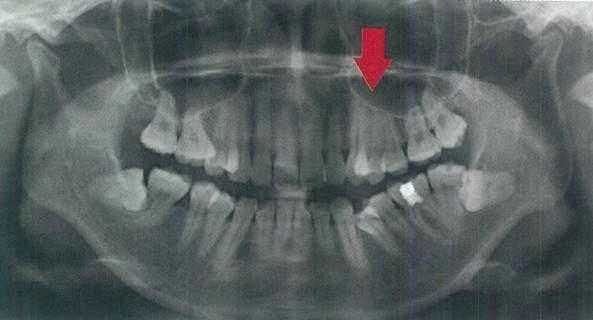

当然要做片切不是说做就做的事儿,正畸医师会结合你的口腔X光片观察牙齿形态和牙槽骨情况进行综合评估,如果发现是严重的牙齿拥挤、牙齿本身太小或者敏感等情况,牙医通常是不会建议进行“邻面去釉”的。